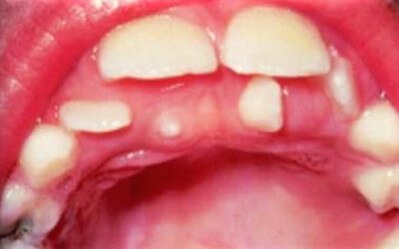

Picture 1: Supernumerary teeth behind the central incisors.

Picture 2: Supernumerary teeth on lateral incisors.